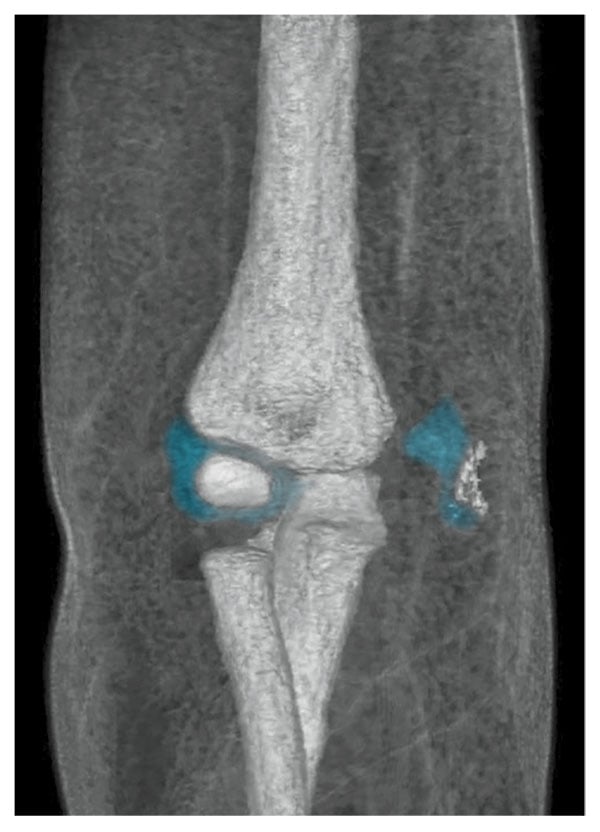

Multiplanar multisequence MR imaging of the right elbow, without gadolinium contrast, was performed with the patient under general anesthesia after several radiographic examinations led to incorrect diagnoses. A 3-D fat-suppressed T1 gradient echo sequence was used to capture volumetric image data and highlight cartilage and bony anatomy. The data were sent to the 3-D Innovation Lab for postprocessing, and technologists used Smart Segmentation (CT Viewer, Intellispace Portal, Philips) techniques, which involved highlighting individual anatomical parts of the elbow and combining them into a 3-D volumetric image. The segmentation tool provides a method to manually segment each part of the anatomy and assign colors to each tissue so that bone and cartilage are easily identified. The 3-D view of the fracture and cartilage revealed their relationship to the displaced osteocartilaginous fracture fragment, which was useful for the radiologist reviewing the MR images as well as for the orthopedic surgeon (see Figure 5). 3-D volume sequences have been used for some time to create coronal, axial, or sagittal reformats from source data. However, the use of 3-D volume sequences to make 3-D volumetric images in musculoskeletal imaging is a new application.

Figure 5.3-D volume renderings of the right elbow, demonstrating a displaced osteocartilaginous medial condyle and epidondyle fracture fragment along the medial aspect of the elbow joint. Images courtesy of the authors